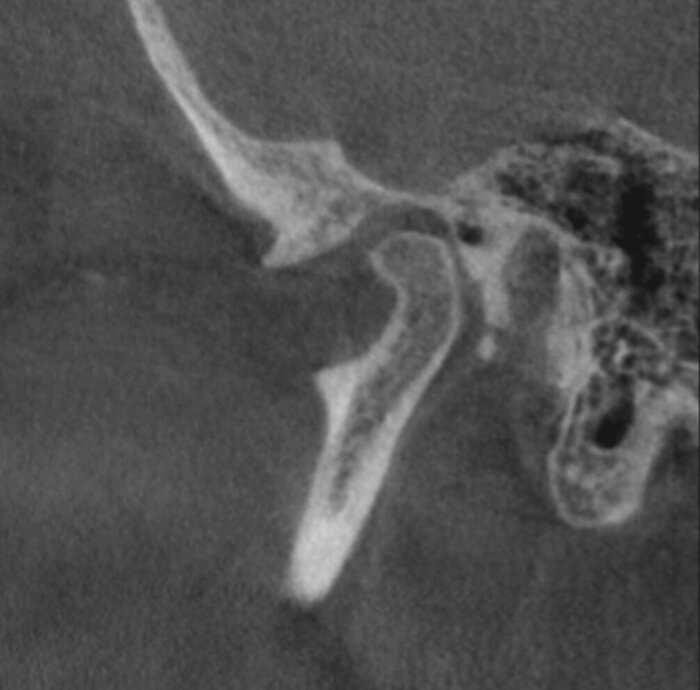

А теперь посмотрим на картину с антагонистами.

Важно - мы не переделывали прикус! А повторили тот, что у пациента уже был, только высоту вернули.

Проверяем попадание в прикус.